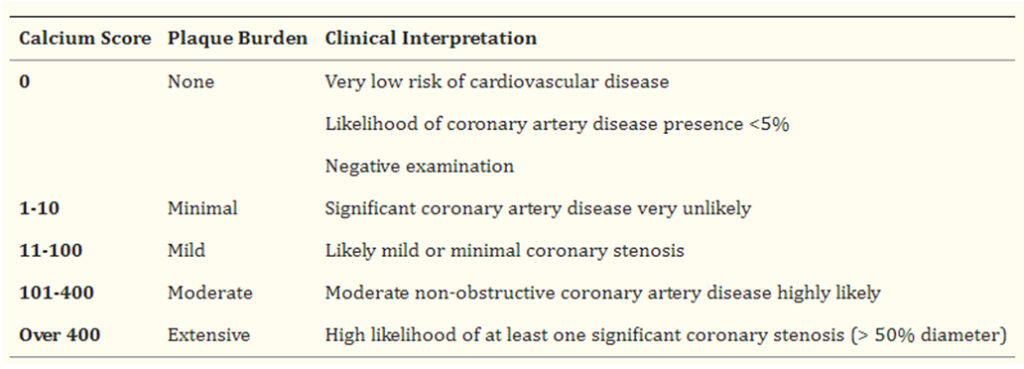

Scoring coronary artery calcium cac tab bmj 1620. Coronary artery calcium scoring. Calcium score jama coronary artery